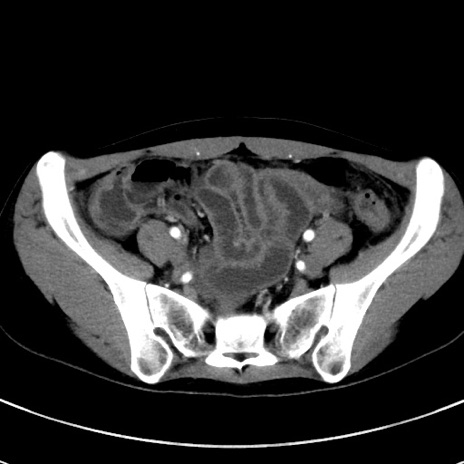

症例17(横断像)

【症例】20歳代女性

【主訴】嘔吐、下腹部痛

【現病歴】昨日夕食後に嘔吐し下腹部痛が出現。本日になっても嘔吐持続し改善しないため来院。

【身体所見】意識清明、BT 37.2℃、BP 108/67mmHg、腹部:平坦、やや硬、下腹部正中から右にかけて圧痛あり、反跳痛軽度あり、tapping pain(+)。

【データ】WBC 13600、CRP 14.94